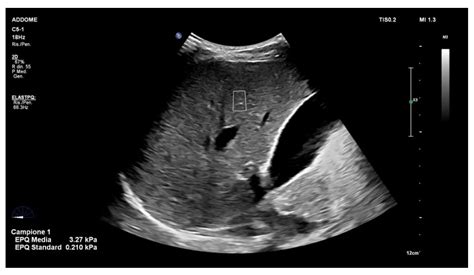

Interpreting the results of a liver ultrasound involves assessing the images for any abnormalities. A normal liver ultrasound will show:

• Size and Shape: The liver should be of normal size and shape, with smooth edges.

• Echogenicity: The liver tissue should have a uniform echogenicity, indicating a healthy structure.

• Blood Flow: Normal blood flow through the liver and its vessels.

• Absence of Abnormalities: No cysts, tumors, or other abnormalities should be present.

• Real-Time Imaging: Ultrasounds provide real-time images, allowing healthcare providers to observe the liver’s structure and function in motion.